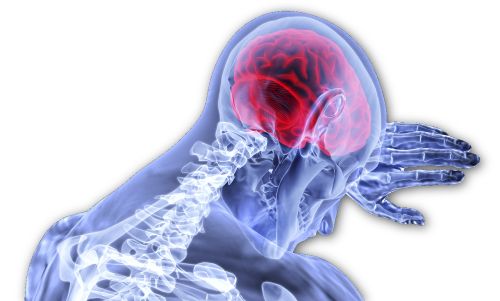

Versuche am Wiener Allgemeinen Krankenhaus mittels spezieller EEG-Verfahren zeigten, dass Hypnose es ermöglicht, die Aktivität des Gehirnes auf einen äusserst kleinen Bereich zu beschränken (blaue Bereiche). Die übrigen Zonen sind dabei sehr inaktiv (grüne Bereiche), auch jene, die für die Schmerzverarbeitung zuständig sind:

(links: Alltags-Aktivität; rechts: hypnotischer Trancezustand; Quelle: AKH)

Nur durch tiefe Meditation z.B. können ähnliche Ruhezustände erreicht werden. Im Wachbewusstsein aber, ja selbst während des Schlafes, steigen Bilder, Erinnerungen und Gedanken auf. In Meditationskursen, beim aus Indien stammenden Pranayama oder beim Autogenen Training wird gelehrt, sich von allen Gedanken zu lösen, dabei jedoch hellwach und konzentriert zu bleiben. Um diesen Zustand zu erreichen, braucht es jedoch viel regelmässige Übung. Bei Hypnose dagegen stellt sich dieser Zustand automatisch ein, und mit dem Gehirn kommt auch der ganze Organismus zur Ruhe - der gesamte Körper läuft, vom Hypnosetherapeuten unterstützt, auf Sparflamme. Die Atmung wird regelmässiger und verlangsamt sich, Herzfrequenz und Blutdruck sinken ebenfalls. Andere, gut erforschte physiologische Veränderungen sind die Erniedrigung der allgemeinen Muskelspannung, eine Abnahme des Stresshormonspiegels, Veränderungen im Blutbild sowie eine geringere Aktivierbarkeit von Reflexen. Hypnose ist dadurch auch in der Lage, physiologische Stressreaktionen zu beeinflussen, wodurch sie eine wirksame Behandlung bei Erkrankungen darstellt, die durch psychische Belastung verursacht oder beeinflusst werden.